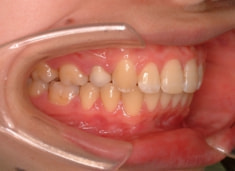

治療開始から1年7ヶ月後

治療後(1年9ヶ月後)